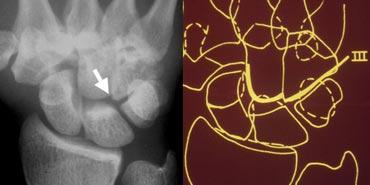

Hình bên trái cho thấy sự gián đoạn của cung cổ tay thứ hai tại khớp thuyền-nguyệt và khớp nguyệt-tháp. Mặc dù có một khoảng hở ở cung thứ nhất, nhưng vẫn có thể vẽ theo một đường cong trơn liên tục, do đó cung I được coi là còn nguyên vẹn.

Sự gián đoạn của cung cổ tay thứ ba được minh họa trong trường hợp tiếp theo ở hình bên trái. Có hiện tượng bậc thang bất thường tại khớp đầu-móc.